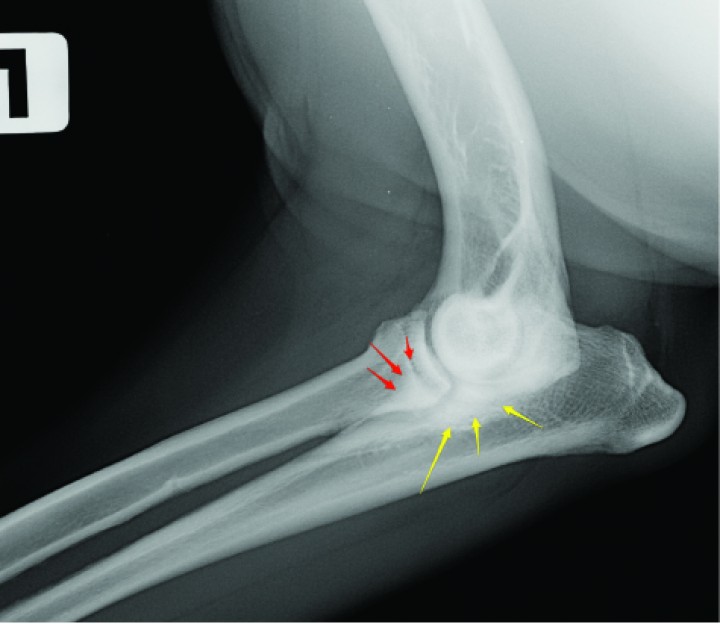

El diagnóstico presuntivo de la displasia de codo y el estudio de la graduación de la misma en la mayoría de animales fue realizado a través de la radiología (Fig. 5).

<p>Radiografía lateral de un Labrador de 11 meses donde se observa una marcada esclerosis subtroclear (flechas amarillas) y difuminación del borde del proceso coronoideo (flechas rojas) indicativas de enfermedad del compartimento medial.</p>

Figura 5

Radiografía lateral de un Labrador de 11 meses donde se observa una marcada esclerosis subtroclear (flechas amarillas) y difuminación del borde del proceso coronoideo (flechas rojas) indicativas de enfermedad del compartimento medial.

Aunque el estudio radiográfico se utiliza como medio de diagnóstico primario de forma generalizada, numerosos estudios cuestionan no sólo su eficacia, sino el valor de los hallazgos.

En los estudios publicados en la literatura de enfermedad coronoidea con un número alto de casos clínicos aportados, el porcentaje de identificación prequirúrgica del EPCM basado solamente en la radiología es muy bajo.[ Fitzpatrick, N. Subtotal coronoid ostectomy (SCO) for the treatment of FMCP: A prospective study of 389 elbows evaluating short and medium term outcome. Proceedings Autumn Scientific Meeting BVOA, Nov 2006, 22-29. ]

La imagen radiológica que lleva al diagnóstico de la enfermedad coronoidea cambia dependiendo de la edad del animal. En los menores de 1 año el signo más visible es una esclerosis subcondral, mientras que en los mayores de un año lo es la difuminación del contorno del proceso coronoides.[ Lau SF, Theyse LF, Voorhout G, Hazewinkel HA. Radiographic, computed tomographic, and arthroscopic findings in labrador retrievers with medial coronoid disease. Vet Surg. 2015;44(4):511-20. [PubMed] ] Igualmente, la eficacia radiológica en el diagnóstico de la enfermedad es un 20% menor en los perros mayores de un año que en los menores de un año.[ Lau SF, Theyse LF, Voorhout G, Hazewinkel HA. Radiographic, computed tomographic, and arthroscopic findings in labrador retrievers with medial coronoid disease. Vet Surg. 2015;44(4):511-20. [PubMed] ]